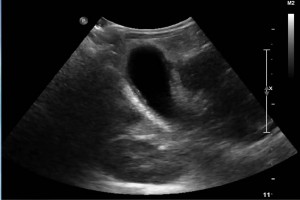

Diplomados en Ultrasonografía